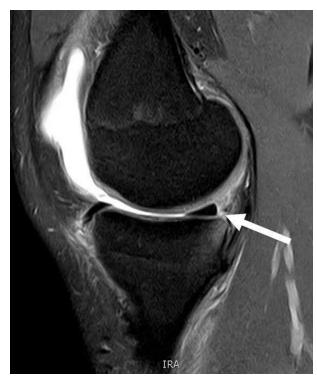

What pathology is seen in this MRI of an 18-year-old male who twisted his knee?

- Posterior horn meniscal tear

- Bucket-handle meniscal tear

What is the significance of the double PCL sign?

- Indicates bucket-handle meniscal tear

What does the white arrow indicate in this image?

- Posterior meniscus horn

What is the diagnosis shown in these images?

- Posterior meniscus horn tear